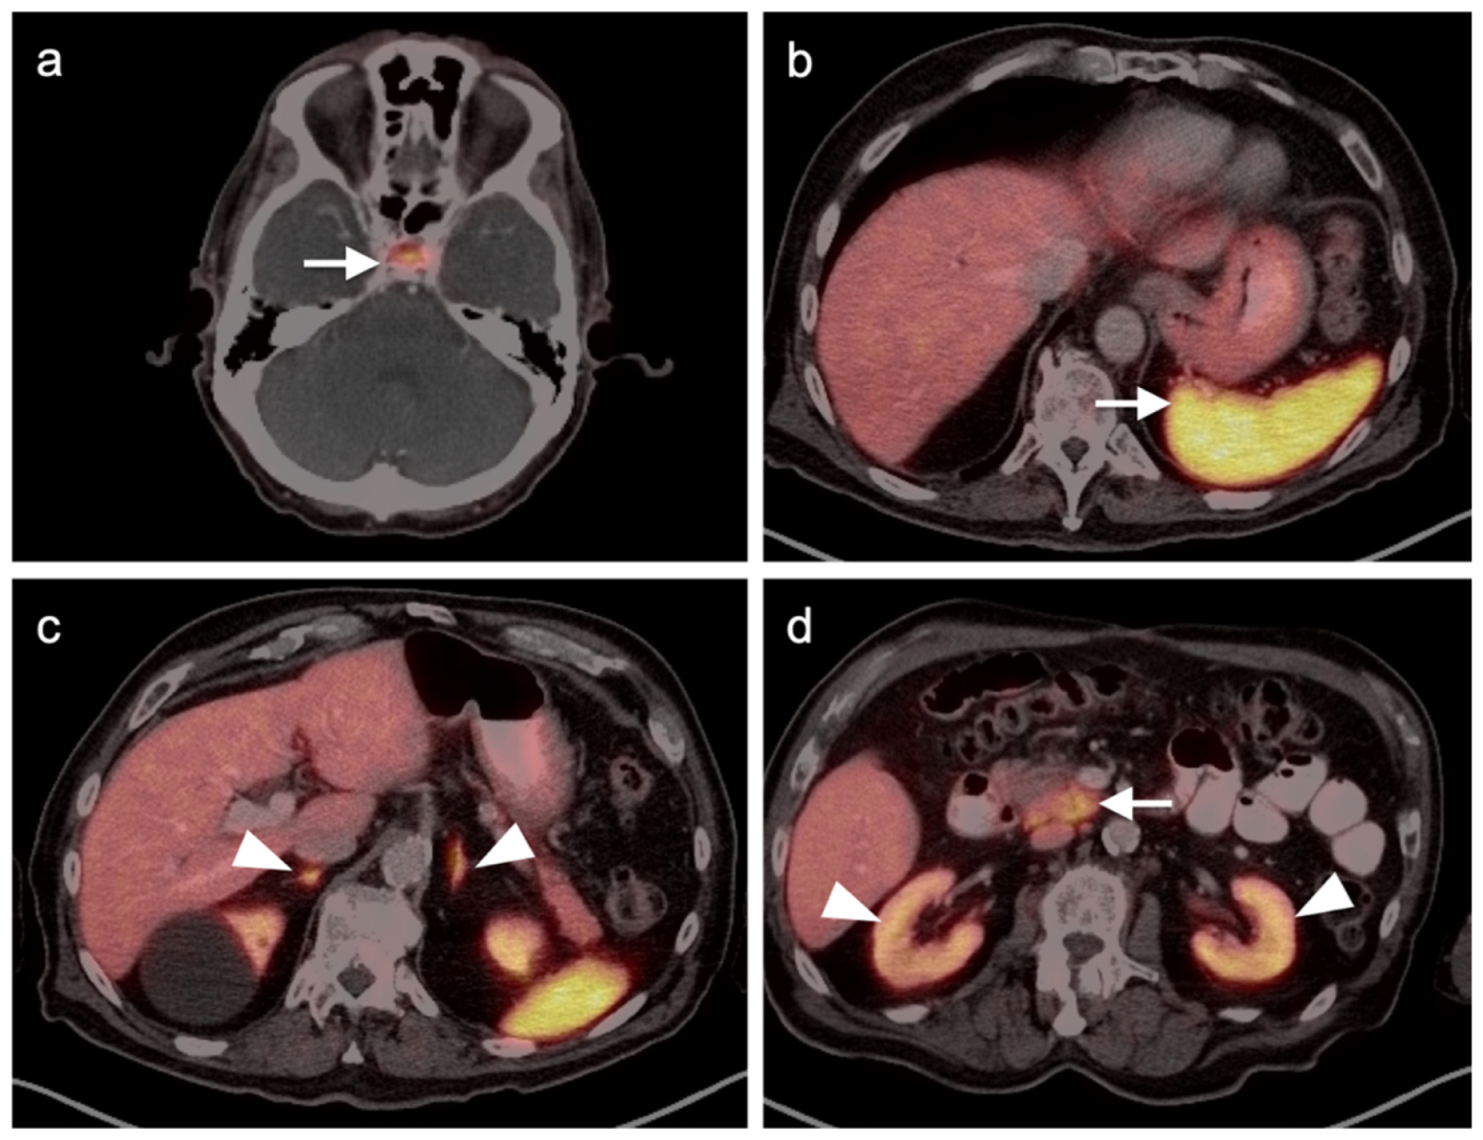

4.5. Pheochromocytoma and Paraganglioma

5. Conclusions

- Webb, H.R.; Latifi, H.R.; Griffeth, L.K. Utility of whole-body (head-to-toe) PET/CT in the evaluation of melanoma and sarcoma patients. Nucl. Med. Commun. 2018, 39, 68–73. [Google Scholar] [CrossRef]